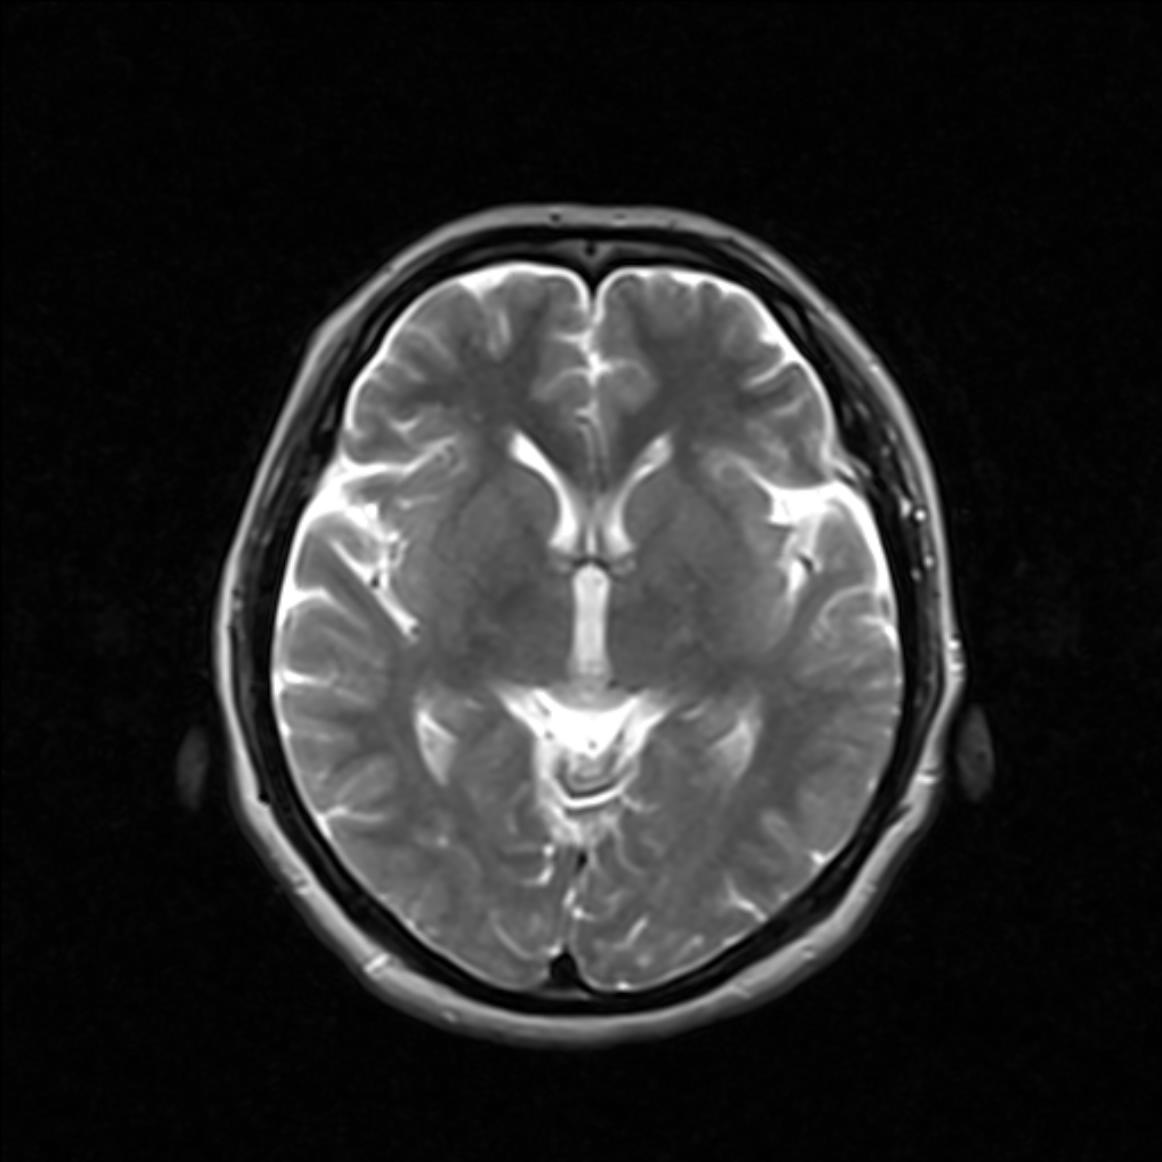

MRI7169:双侧脑室前角旁异常信号。

女,49岁,双侧脑室前角旁异常信号。

考虑:双侧脉络丛可能。

脉络丛钙化

考虑:双侧脉络丛钙化。

膜络丛钙化。